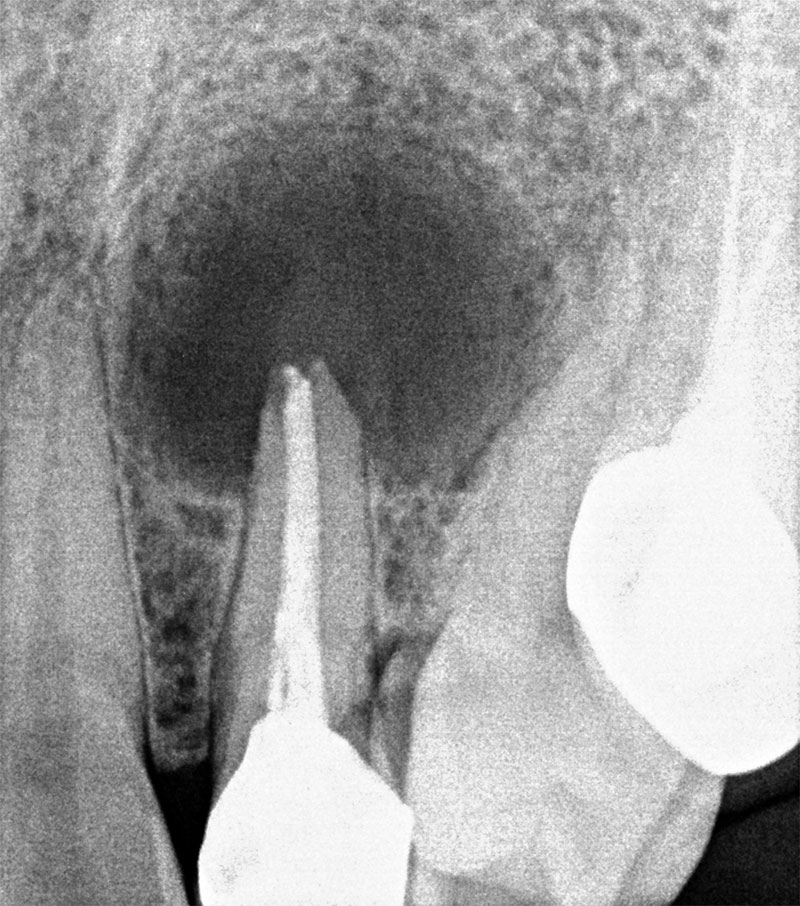

치료 전

의도적 발치 직후 뿌리 끝 염증 관찰

치료 1년 반 후